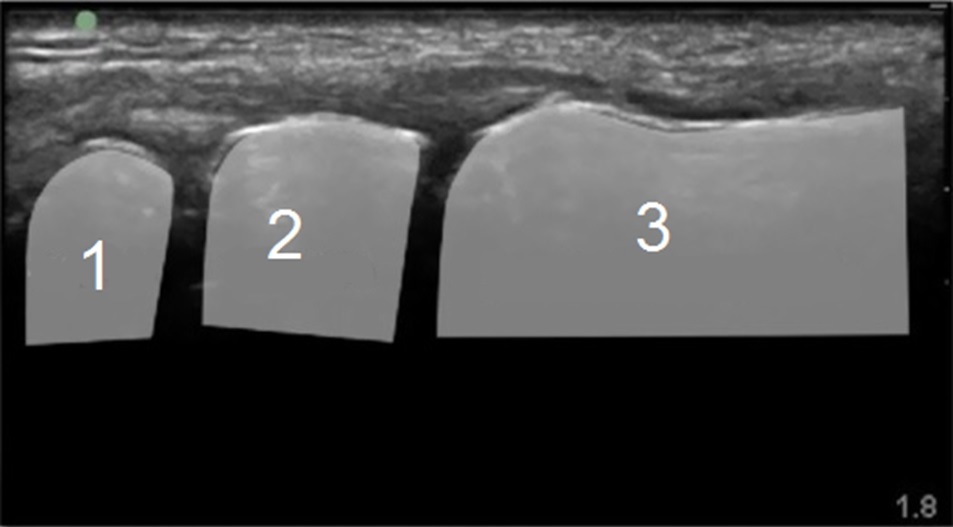

手首の第1CMC関節注射解剖1の画像

舟状骨

大菱形骨

第1中手骨の基部